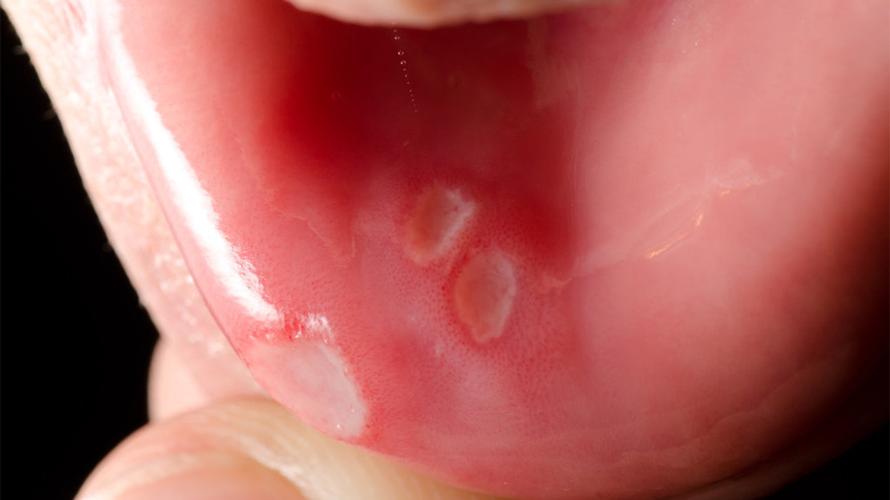

最常见的原因:口腔黏液腺囊肿

这是最可能的情况,它是由口腔内的小唾液腺(黏液腺)的导管堵塞后,分泌的黏液无法排出,积聚在腺体或其周围组织形成的。

- 特点:

- 外观: 呈现半球形,表面光滑,颜色为淡紫色或透明,像一颗水珠。

- 大小: 直径通常在几毫米到一厘米左右。

- 感觉: 一般不痛,除非囊肿较大或咬到。

- 位置: 最常见于下唇内侧,但也可能出现在舌尖、口内颊黏膜等部位。

- 变化: 有时可能会因为咬到而自行破裂,流出一些无色透明的黏稠液体,然后囊肿会暂时变小或消失,但不久后可能在原位或附近再次长出,容易复发。